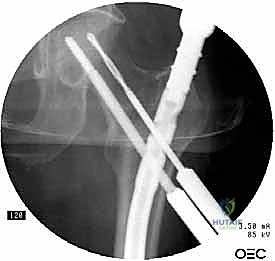

5. تثبيت عنق ورأس الفخذ (المسمار الرأسي)

من خلال ذراع توجيه متصلة بالمسمار الرئيسي، يتم إحداث ثقب في عنق ورأس عظمة الفخذ. يتم إدخال المسمار الرأسي (Cephalic Screw) السميك ليمسك برأس الفخذ بقوة ويسحبه نحو المسمار الرئيسي، مما يضغط الكسر (Compression) ويحفز التئام العظام بسرعة.

6. التثبيت السفلي (Distal Locking)

لضمان عدم دوران العظمة حول المسمار، يتم إدخال مسمار أو مسمارين صغيرين في الجزء السفلي من المسمار النخاعي عبر شقوق جلدية دقيقة جداً (لا تتجاوز 1 سم).